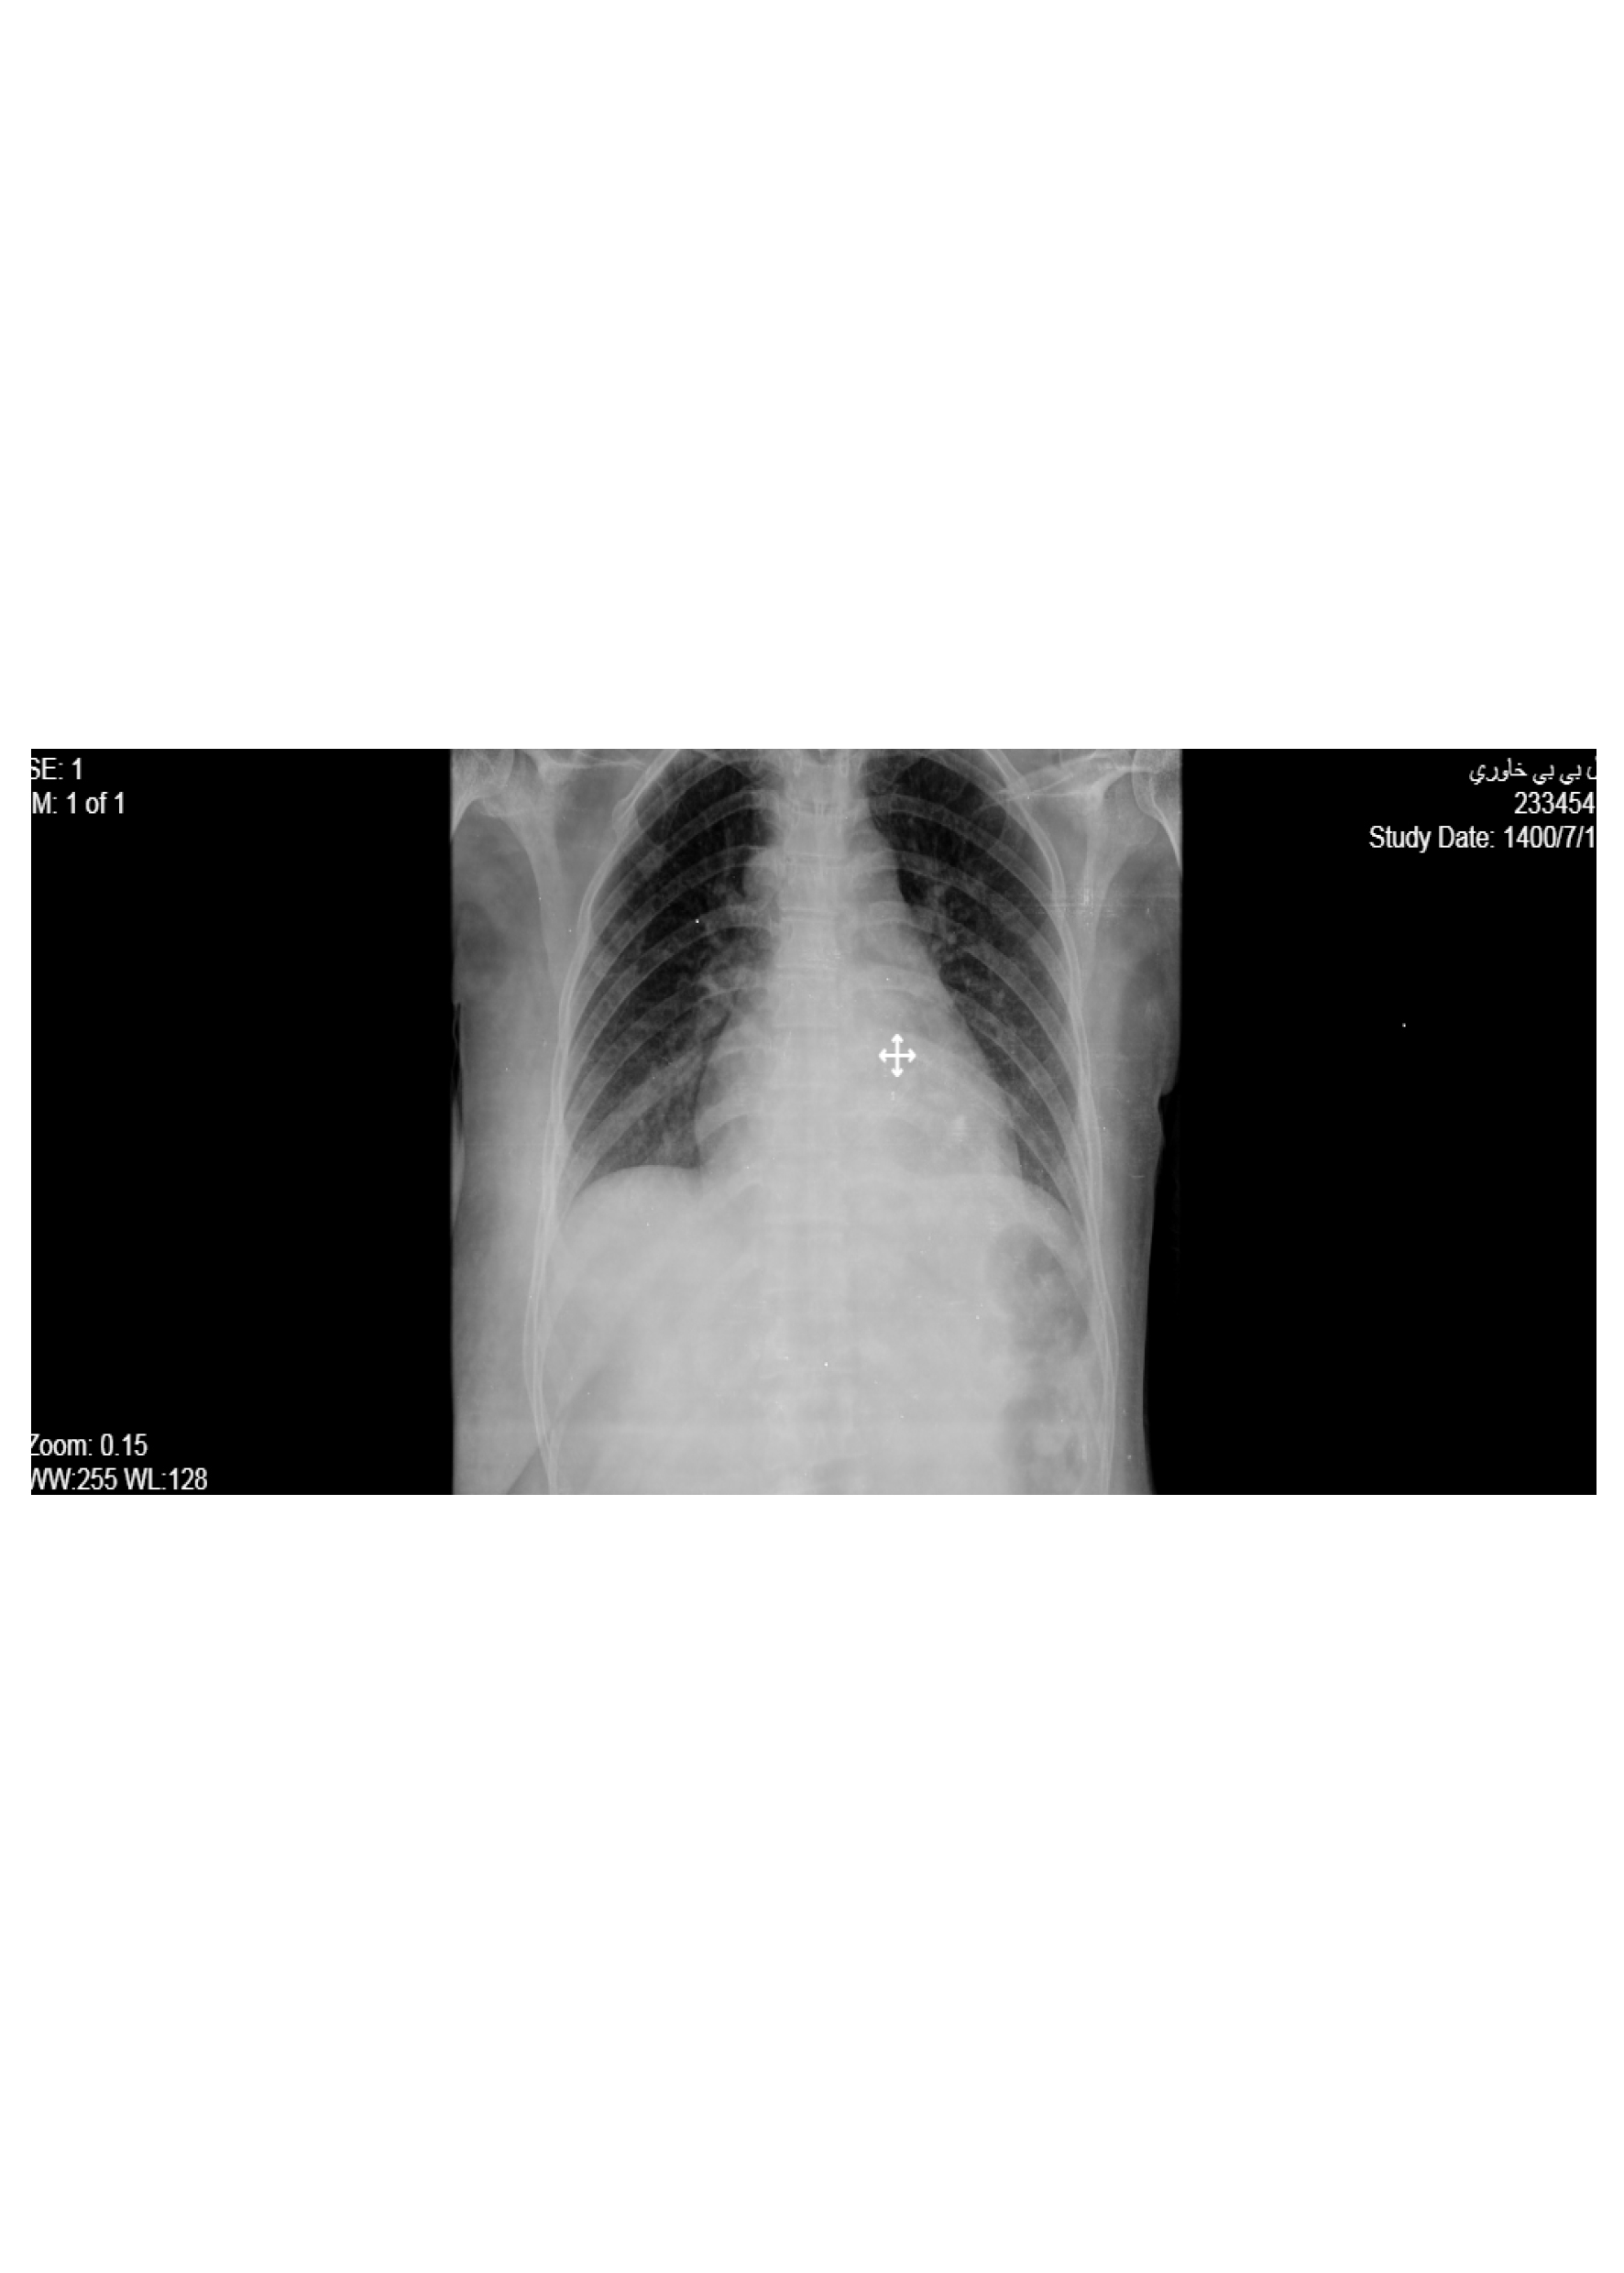

Figure 4. Chest x-ray after mastectomy without arenchymal and rib involvement.